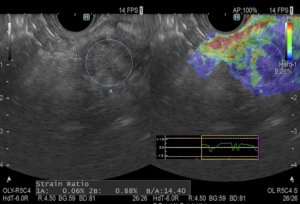

スクリーンショット 2021-02-23 22.11.25